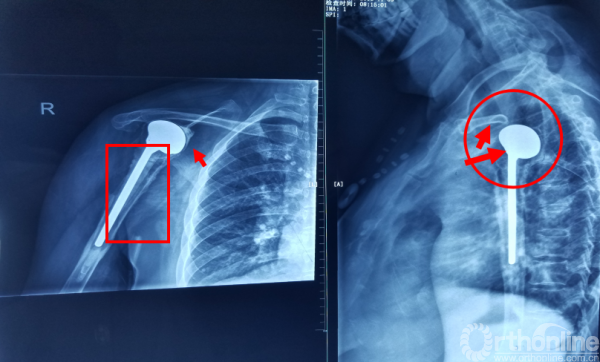

二次入院时X线检查

1.松动?感染?松动+感染?

X片:假体周围透亮带;骨溶解;骨膜新骨形成。铟白细胞骨扫描(更为精确)

注意事项:  肱骨头内移至喙突处,位于后内侧下方已有骨桥连接